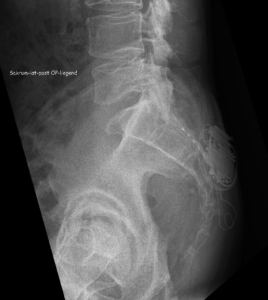

Bonus: the spinal cord stimulation

Jeroen talked about his experience with the spinal cord stimulation. In this procedure, an electrode (in th eshape of a needle) is placed internally near the spinal cord. Here it directly desrupts and in that way decreases the pain signals from the painful area to the brain through low frequency electrical currents, through a stimulator under the skin. This device can be charged through the skin and controlled by a remote control. It is more or less comparable with TENS which is external stimulation on the skin and through the peripheral nervous system. Spinal cord stimulation works internally and as the name indicates, directly on the central nervous system.

These are the pictures shared by Jeroen after his surgery. The dotted line is the electrode, the implanted device (stimulator) that sends the current is the round object.

This procedure only targets the pain, so it doesn’t solve the underlying problem itself and only works as long as the current is applied. On the other hand it is fully reversible by removing the device and has no side effects like you have with medication. Since it is minimal invasive surgery, there is hardly any tissue damage or scar tissue. It starts with a test period of 1 week, where only the electrode is inserted and the device remains external. After the trial period the patient and the surgeon evaluate and decide on a

permanent implant.